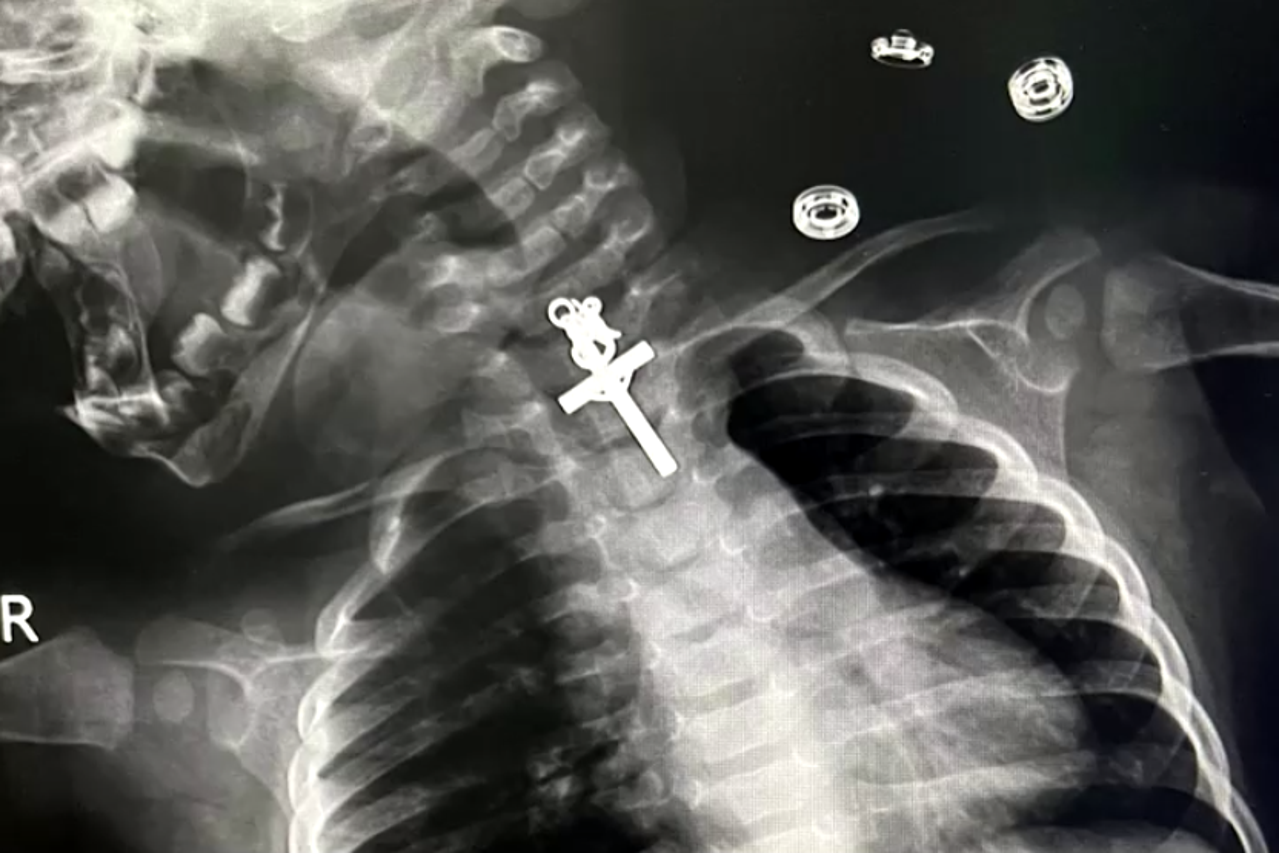

Video sadržaj NESVAKIDAŠNJI ZAHVAT VIDEO Peruanski liječnici iz grla malene djevojčice izvukli raspelo: 'Ovo je dar, blagoslov, čudo' Majka je dovela djevojčicu u bolnicu nakon što je primijetila da malena osjeća nelagodu